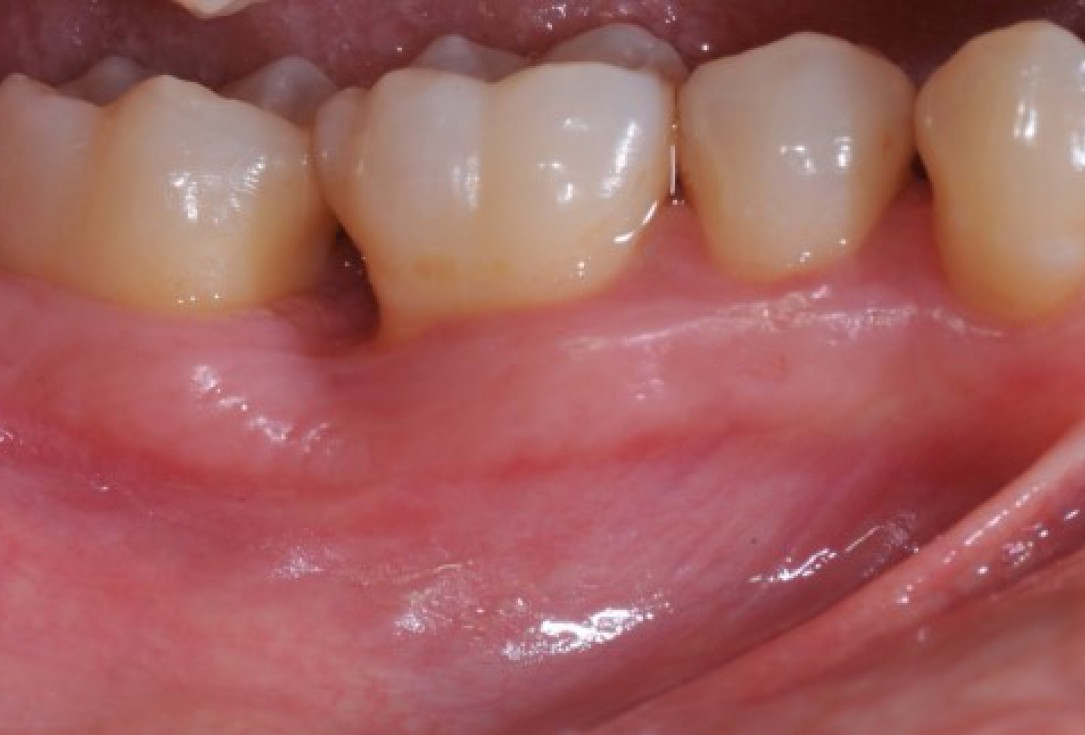

Pre-operative clinical situation. Shallow multiple adjacent gingival recessions in the first quadrant.